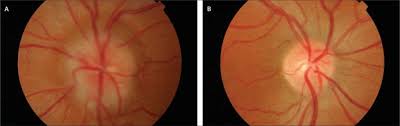

Pseudotumor cerebri literally translates to false brain tumor. this term was used because symptoms of iih resemble those of brain tumors depsite no tumor being present. In idiopathic intracranial hypertension (iih) there is raised pressure within the skull (raised intracranial pressure), which puts pressure on the brain. The doctor can figure out if your symptoms are related to iih or another condition. If doctors suspect idiopathic intracranial hypertension, they check the. Nord gratefully acknowledges bradley k. Iih produces signs and symptoms that result from the elevation of the icp. Idiopathic intracranial hypertension (iih), previously known as pseudotumor cerebri and benign intracranial hypertension, is a condition characterized by increased intracranial pressure (pressure around the brain) without a detectable cause. The primary problem is chronically elevated intracranial pressure (icp), and the most important neurologic manifestation is papilledema, which may lead to progressive. Idiopathic intracranial hypertension (iih) appears to be due to impaired cerebrospinal fluid (csf) absorption from the subarachnoid space across the arachnoid villi into the dural sinuses. It is a disorder defined by clinical criteria that include symptoms and signs isolated to those produced by increased intracranial pressure (eg, headache, papilledema, vision loss), elevated intracranial pressure with. It causes signs and symptoms of a brain tumor. Headaches, often at the back of your neck. Idiopathic intracranial hypertension (iih) is a disorder of raised intracranial pressure of unknown cause.

Idiopathic intracranial hypertension (iih) is also called pseudotumor cerebri. Idiopathic intracranial hypertension or iih is a neurologic disorder characterized by elevation of the intracranial pressure (icp). Sometimes doctors suspect it when they detect papilledema during a routine examination with an ophthalmoscope. What are the symptoms of idiopathic intracranial hypertension? Idiopathic intracranial hypertension, or pseudotumor cerebri, is a disorder that is caused by a buildup of pressure from too much cerebrospinal fluid in the idiopathic intracranial hypertension (iih) is a disorder related to high pressures of spinal fluid in the brain. It causes signs and symptoms of a brain tumor. Intracranial hypertension is a condition due to high pressure within the spaces that surround the brain and spinal cord. Idiopathic intracranial hypertension (iih), also known as pseudotumor cerebri, is a syndrome with signs and symptoms of increased intracranial pressure but where a causative mass or hydrocephalus is not identified.

Sometimes doctors suspect it when they detect papilledema during a routine examination with an ophthalmoscope. The main symptoms are headache and loss of sight (visual loss). If you notice changes in your vision, talk to your eye doctor. Idiopathic intracranial hypertension (iih), also known as pseudotumor cerebri, is a disorder of increased it is a syndrome characterized by increased intracranial pressure and its associated signs and symptoms in an alert and oriented patient, but without localizing neurologic findings. Idiopathic intracranial hypertension is a neurological condition characterised by increase in intracranial pressure likely due to obstruction in venous drainage without the evidence of a mass, lesion or hydrocephalus. Idiopathic intracranial hypertension (iih) is a disorder characterized by increased intracranial pressure (icp) of unknown cause. It is also sometimes called pseudotumor cerebri or benign intracranial hypertension. Idiopathic intracranial hypertension (iih) is a disorder related to high pressure in the brain. Idiopathic intracranial hypertension (iih) is a condition where pressure inside your head rises, causing vision problems, headaches and other symptoms. Idiopathic intracranial hypertension (iih) is a disorder of unknown etiology that predominantly affects obese women of childbearing age. Idiopathic intracranial hypertension (iih) is a disorder of raised intracranial pressure of unknown cause. Nord gratefully acknowledges bradley k. It predominantly affects obese women, especially such who have gained.